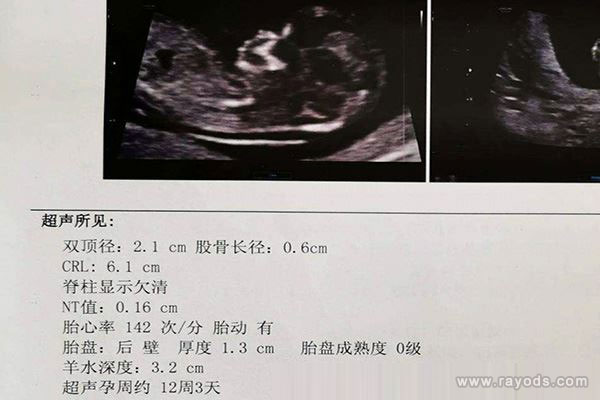

说到产检单子,相信不少过来人都会第一时间想到nt单子吧,据说nt单子上有关于男女宝宝性别的暗示,用不少已验证宝妈的结个人经历来看,准确率还蛮高的,特别是nt单子上的数值和图片,都不容错过。一般来说,nt检查会在孕12周的时候进行,这个时候最为合适,数据稳定而且很准。那通过孕12周nt单子上的nt值看男女准不准呢?下面就随本文一起来揭晓答案吧。

据不少已生验证的宝妈透露城称,通过nt单子上的nt值看男女很准,其有85%的准确率!据称,如果nt单子上的nt值大于1.5的话,生男孩的几率大,反之如果nt单子上的nt值小于1的话,生女孩的几率大。

相比较之下,nt值处于1-1.4之间的,生男生女的几率都一样。已生宝妈就总结出了这样的结论,nt值在正常范围内(3mm)偏高的话生男孩,偏低的生女孩。

而对于这样的一个结论,过来人的解释是因为男孩的皮肤要比女孩的皮肤厚一些,因此nt值也要偏高一些。之后也有不少的孕妈和宝妈都验证了,都表示准确率高,有85%以上。